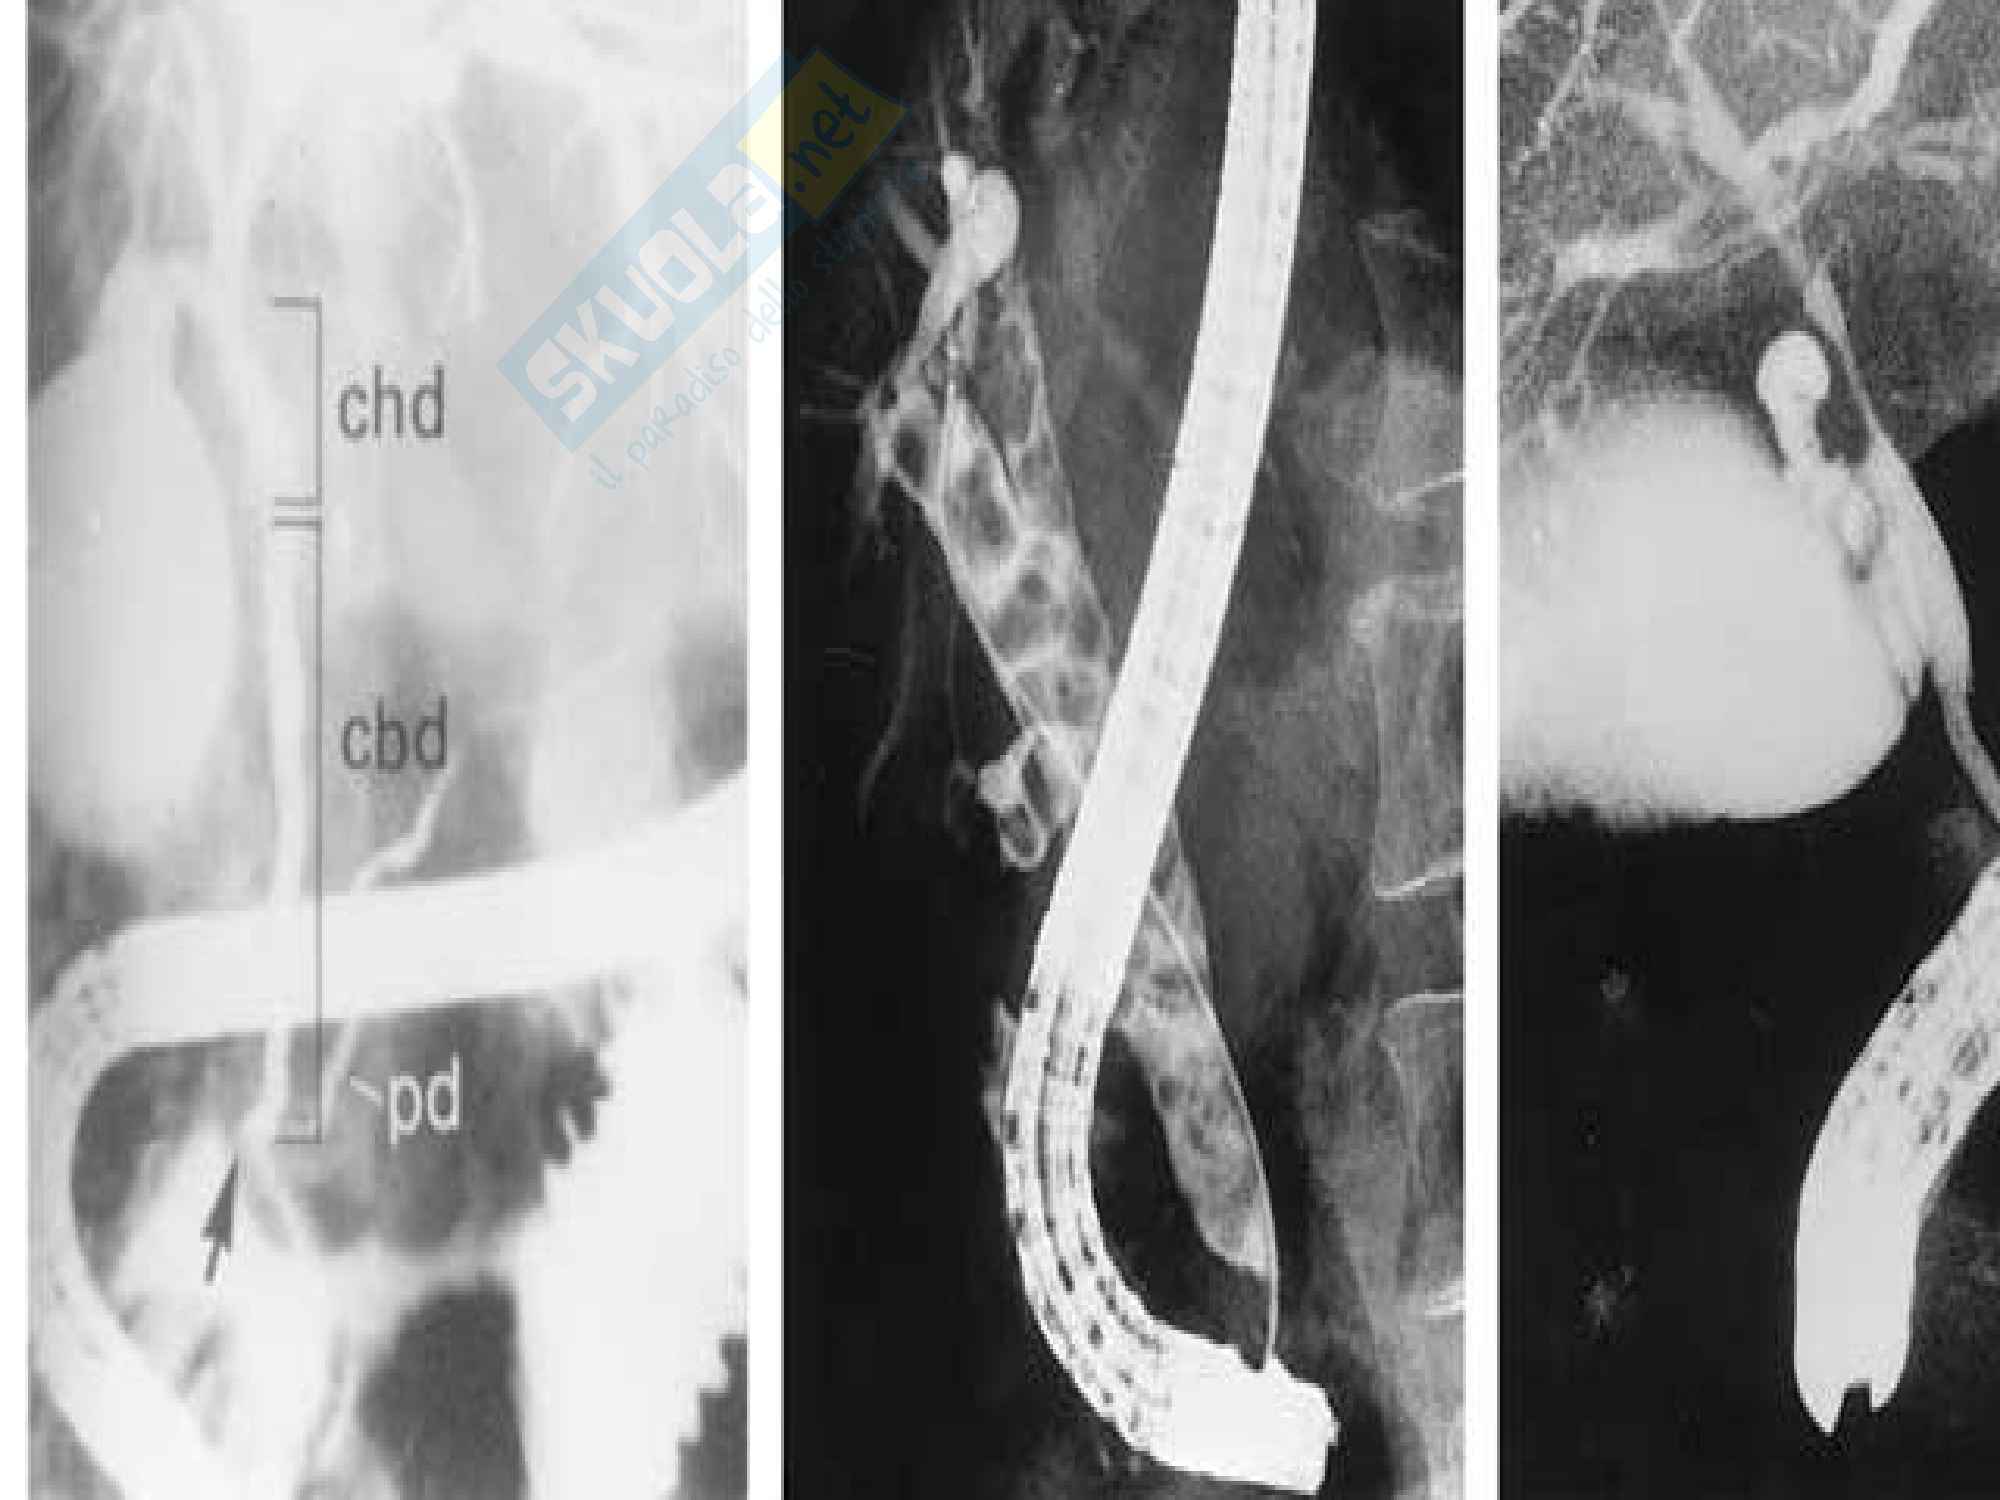

Une cholangiographie rétrograde par voie endoscopique (ERCP) un tube souple, le duodénoscope, est introduit par la bouche, puis passe dans l’œsophage, l'estomac pour atteindre le duodénum, la première partie de l'intestin. Cholangite prise en charge des patients Diagnostic Pour poser le diagnostic de la maladie, différents examens peuvent être menés des analyses sanguines ;;. Colangite sclerosante primitiva Il ruolo del microbioma intestinale Uno studio condotto in Norvegia ha messo in evidenza importanti differenze tra il microbioma intestinale dei pazienti con.

Malattie delle vie biliari litiasi, colangite, sclerosante, cirrosi biliare e pancreatiti Appunti schematici delle lezioni integrati con ulteriori info dai casi clinici e basati sul Rugarli. Une cholangiographie rétrograde par voie endoscopique (ERCP) un tube souple, le duodénoscope, est introduit par la bouche, puis passe dans l’œsophage, l'estomac pour atteindre le duodénum, la première partie de l'intestin. Invece, le più importanti entità nosologiche primitive, che attengono alla patologia colestatica, sono la cirrosi biliare primitiva (CBP), oggi definita colangite biliare primitiva, e la colangite sclerosante primitiva (CSP) Entrambe sono sindromi colestatiche croniche, caratterizzate da una fibrosi infiammatoria dei dotti biliari, intra.